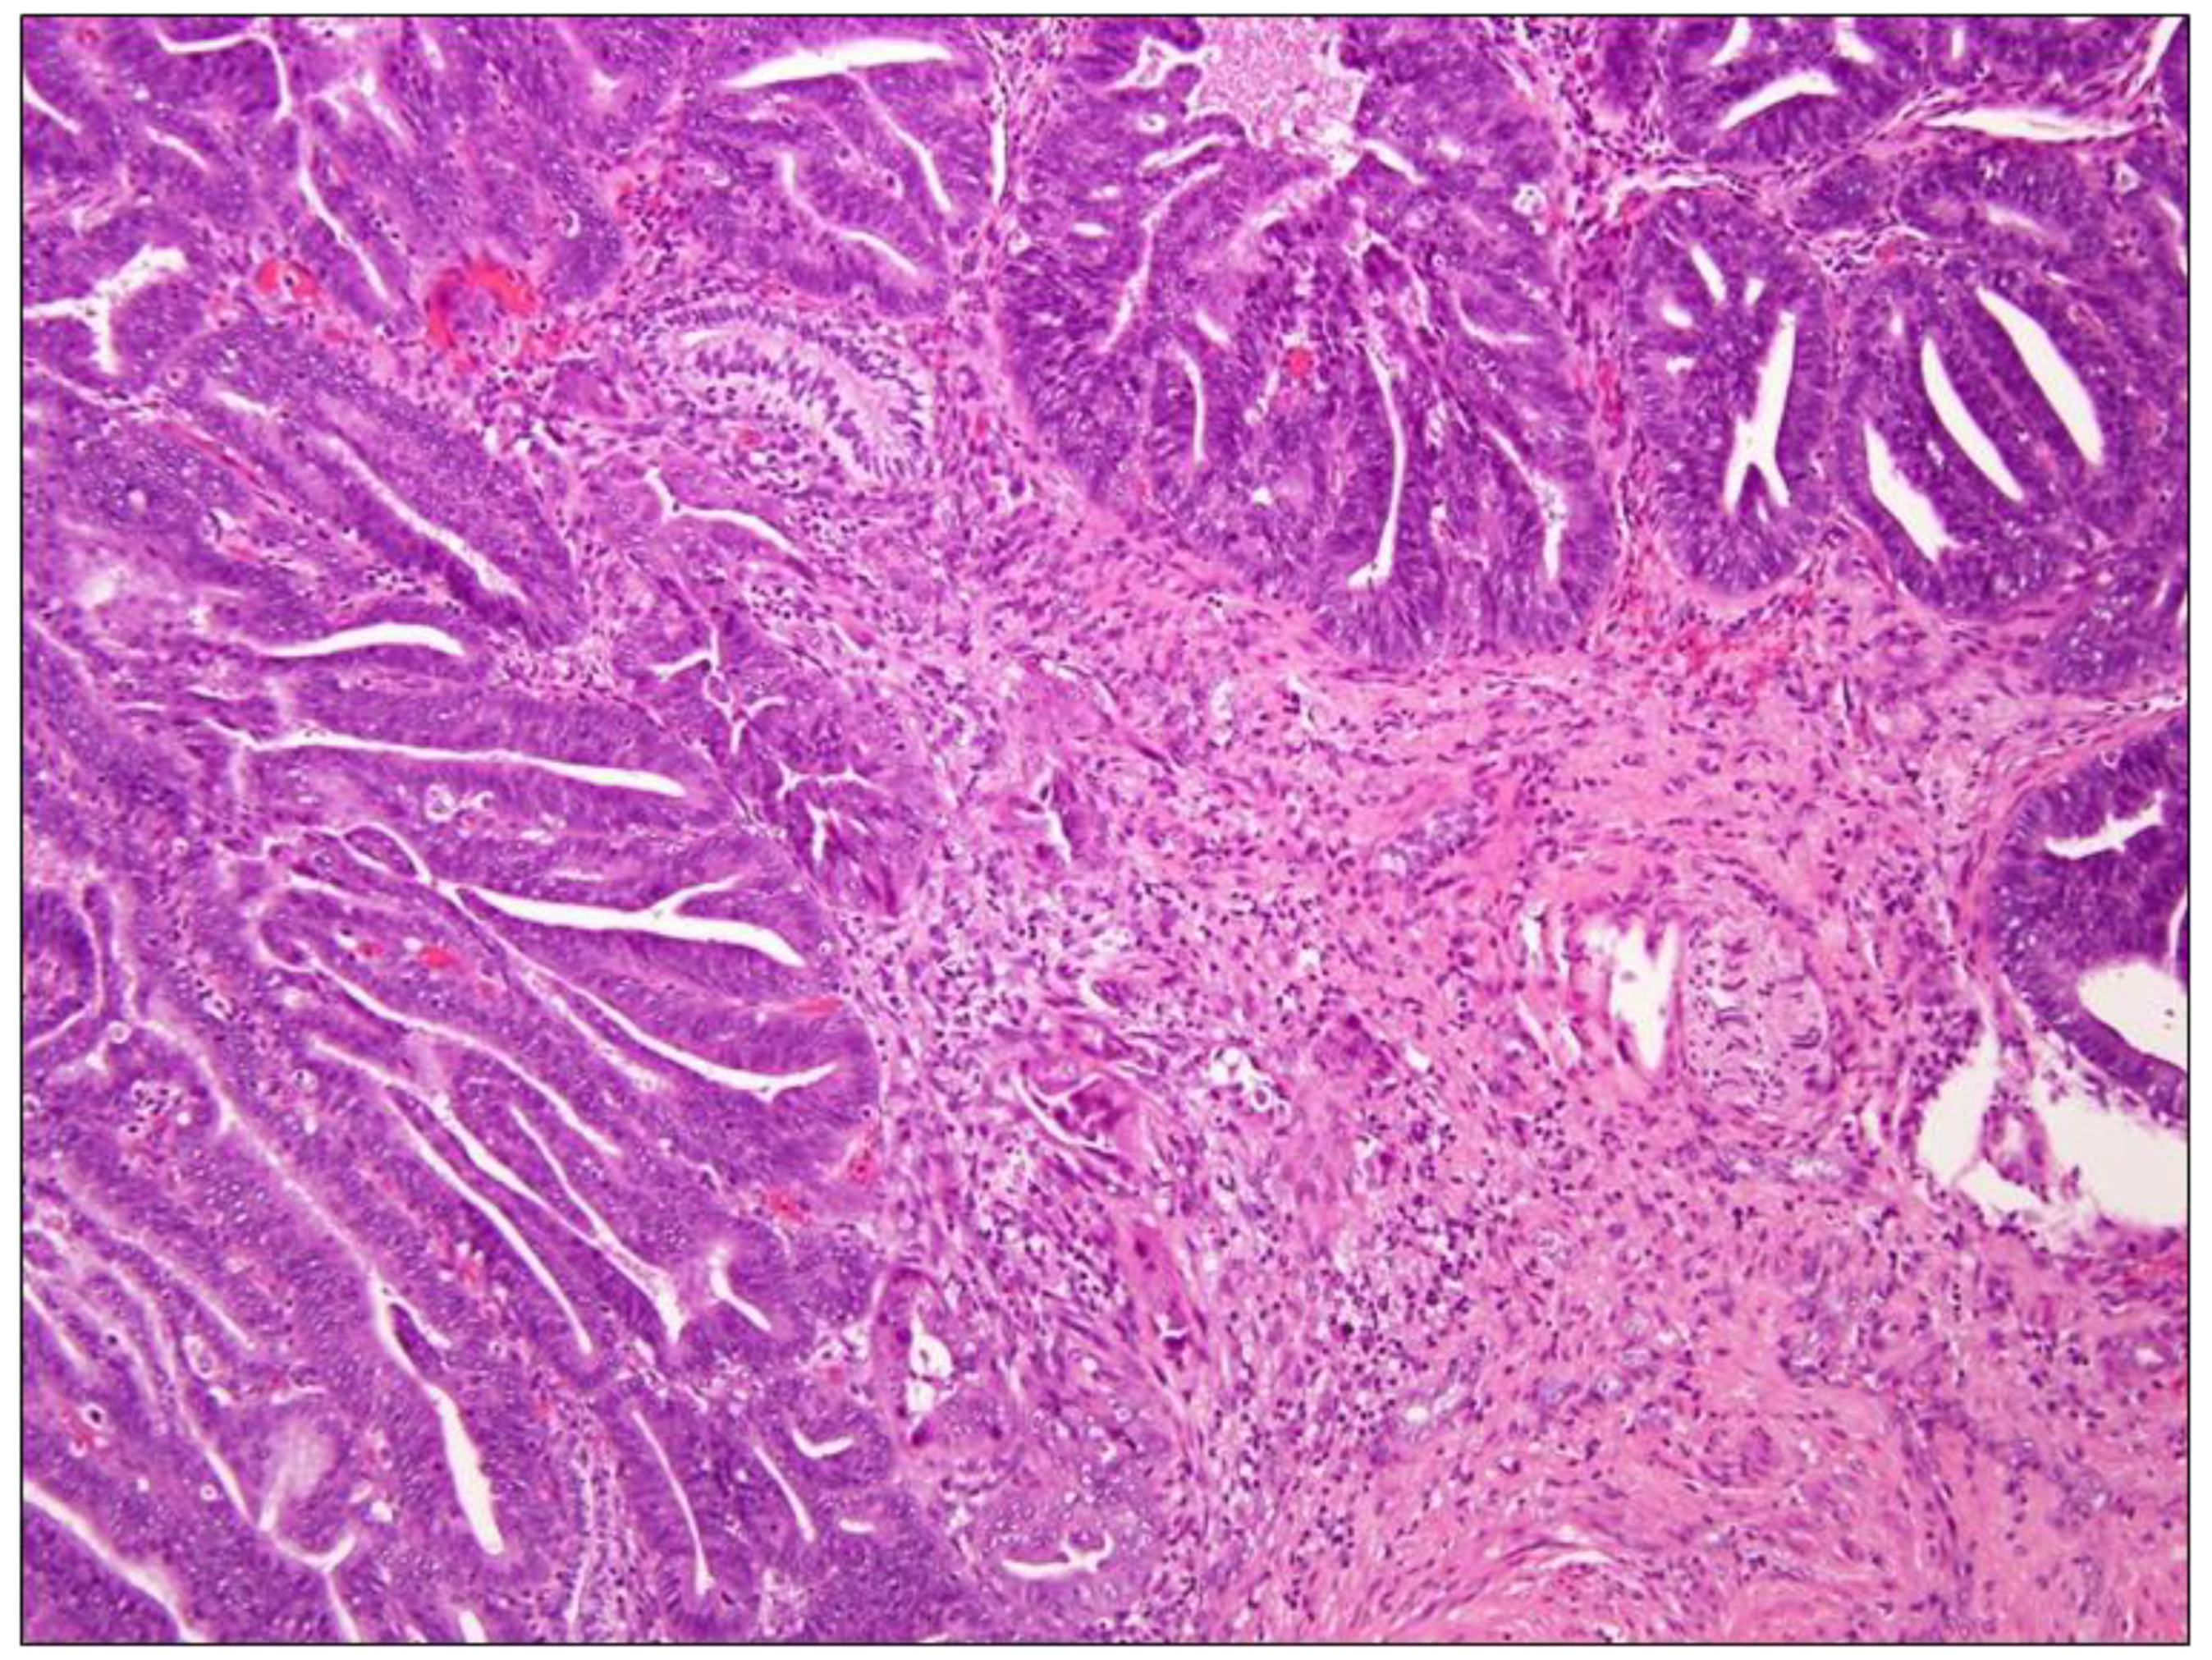

3.2.1. Endometrioid ADC

Primary endometrioid ADC (Figure 3) is defined by the WHO as ADC arising from the cervix that has endometrioid morphologic features, such as tumor cells that are lacking mucin with a scant, deeply eosinophilic cytoplasm resembling endometrial-type epithelium. These tumors are rare and account for no more than 5% of all cervical ADCs [20]. Similar to the ones previously mentioned, they seem not associated with high-risk HPV [2]. Endometrioid cervical ADCs are typically and strongly p16-positive in contrast to tumors of endometrial origin, which most often have a patchy pattern of p16 expression [26].

Figure 3. Endometroid carcinoma, Hematoxylin-Eosin, 10× magnification. The panel shows endometroid carcinoma of the cervix whose morphology is similar to endometrioid adenocarcinoma arising in the uterine corpus. In particular, key features are the confluent or back-to-back glands lacking intervening stroma, with cribriform or microacinar configurations and complex papillary, micropapillary, or villoglandular structures. Nuclear rounding, enlargement with large nucleoli, and loss of polarity and cytoplasmic eosinophilia are also visible.